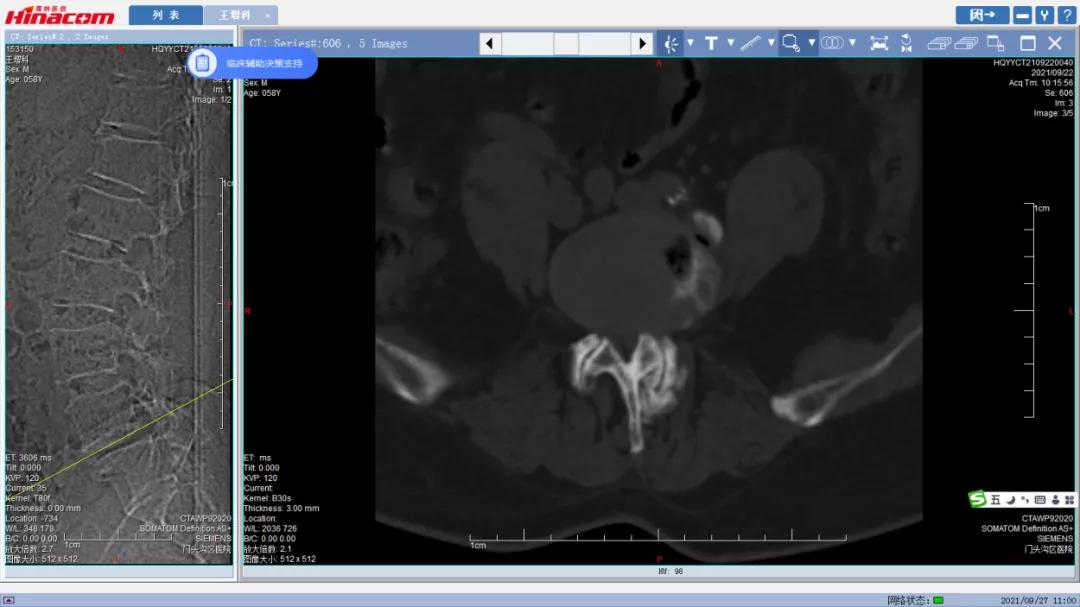

腰45椎间盘--术前CT